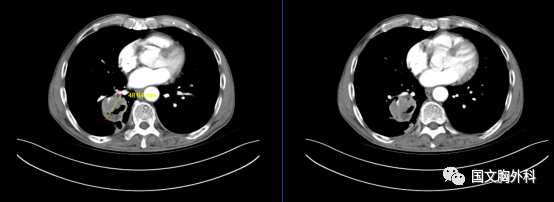

入院時胸部CT,提示:胸部CT平掃+增強:右肺下葉占位,符合肺癌表現(xiàn),伴周圍阻塞性肺炎。縱隔、右肺門稍大淋巴結(jié),轉(zhuǎn)移不除外。

治療前 ↓